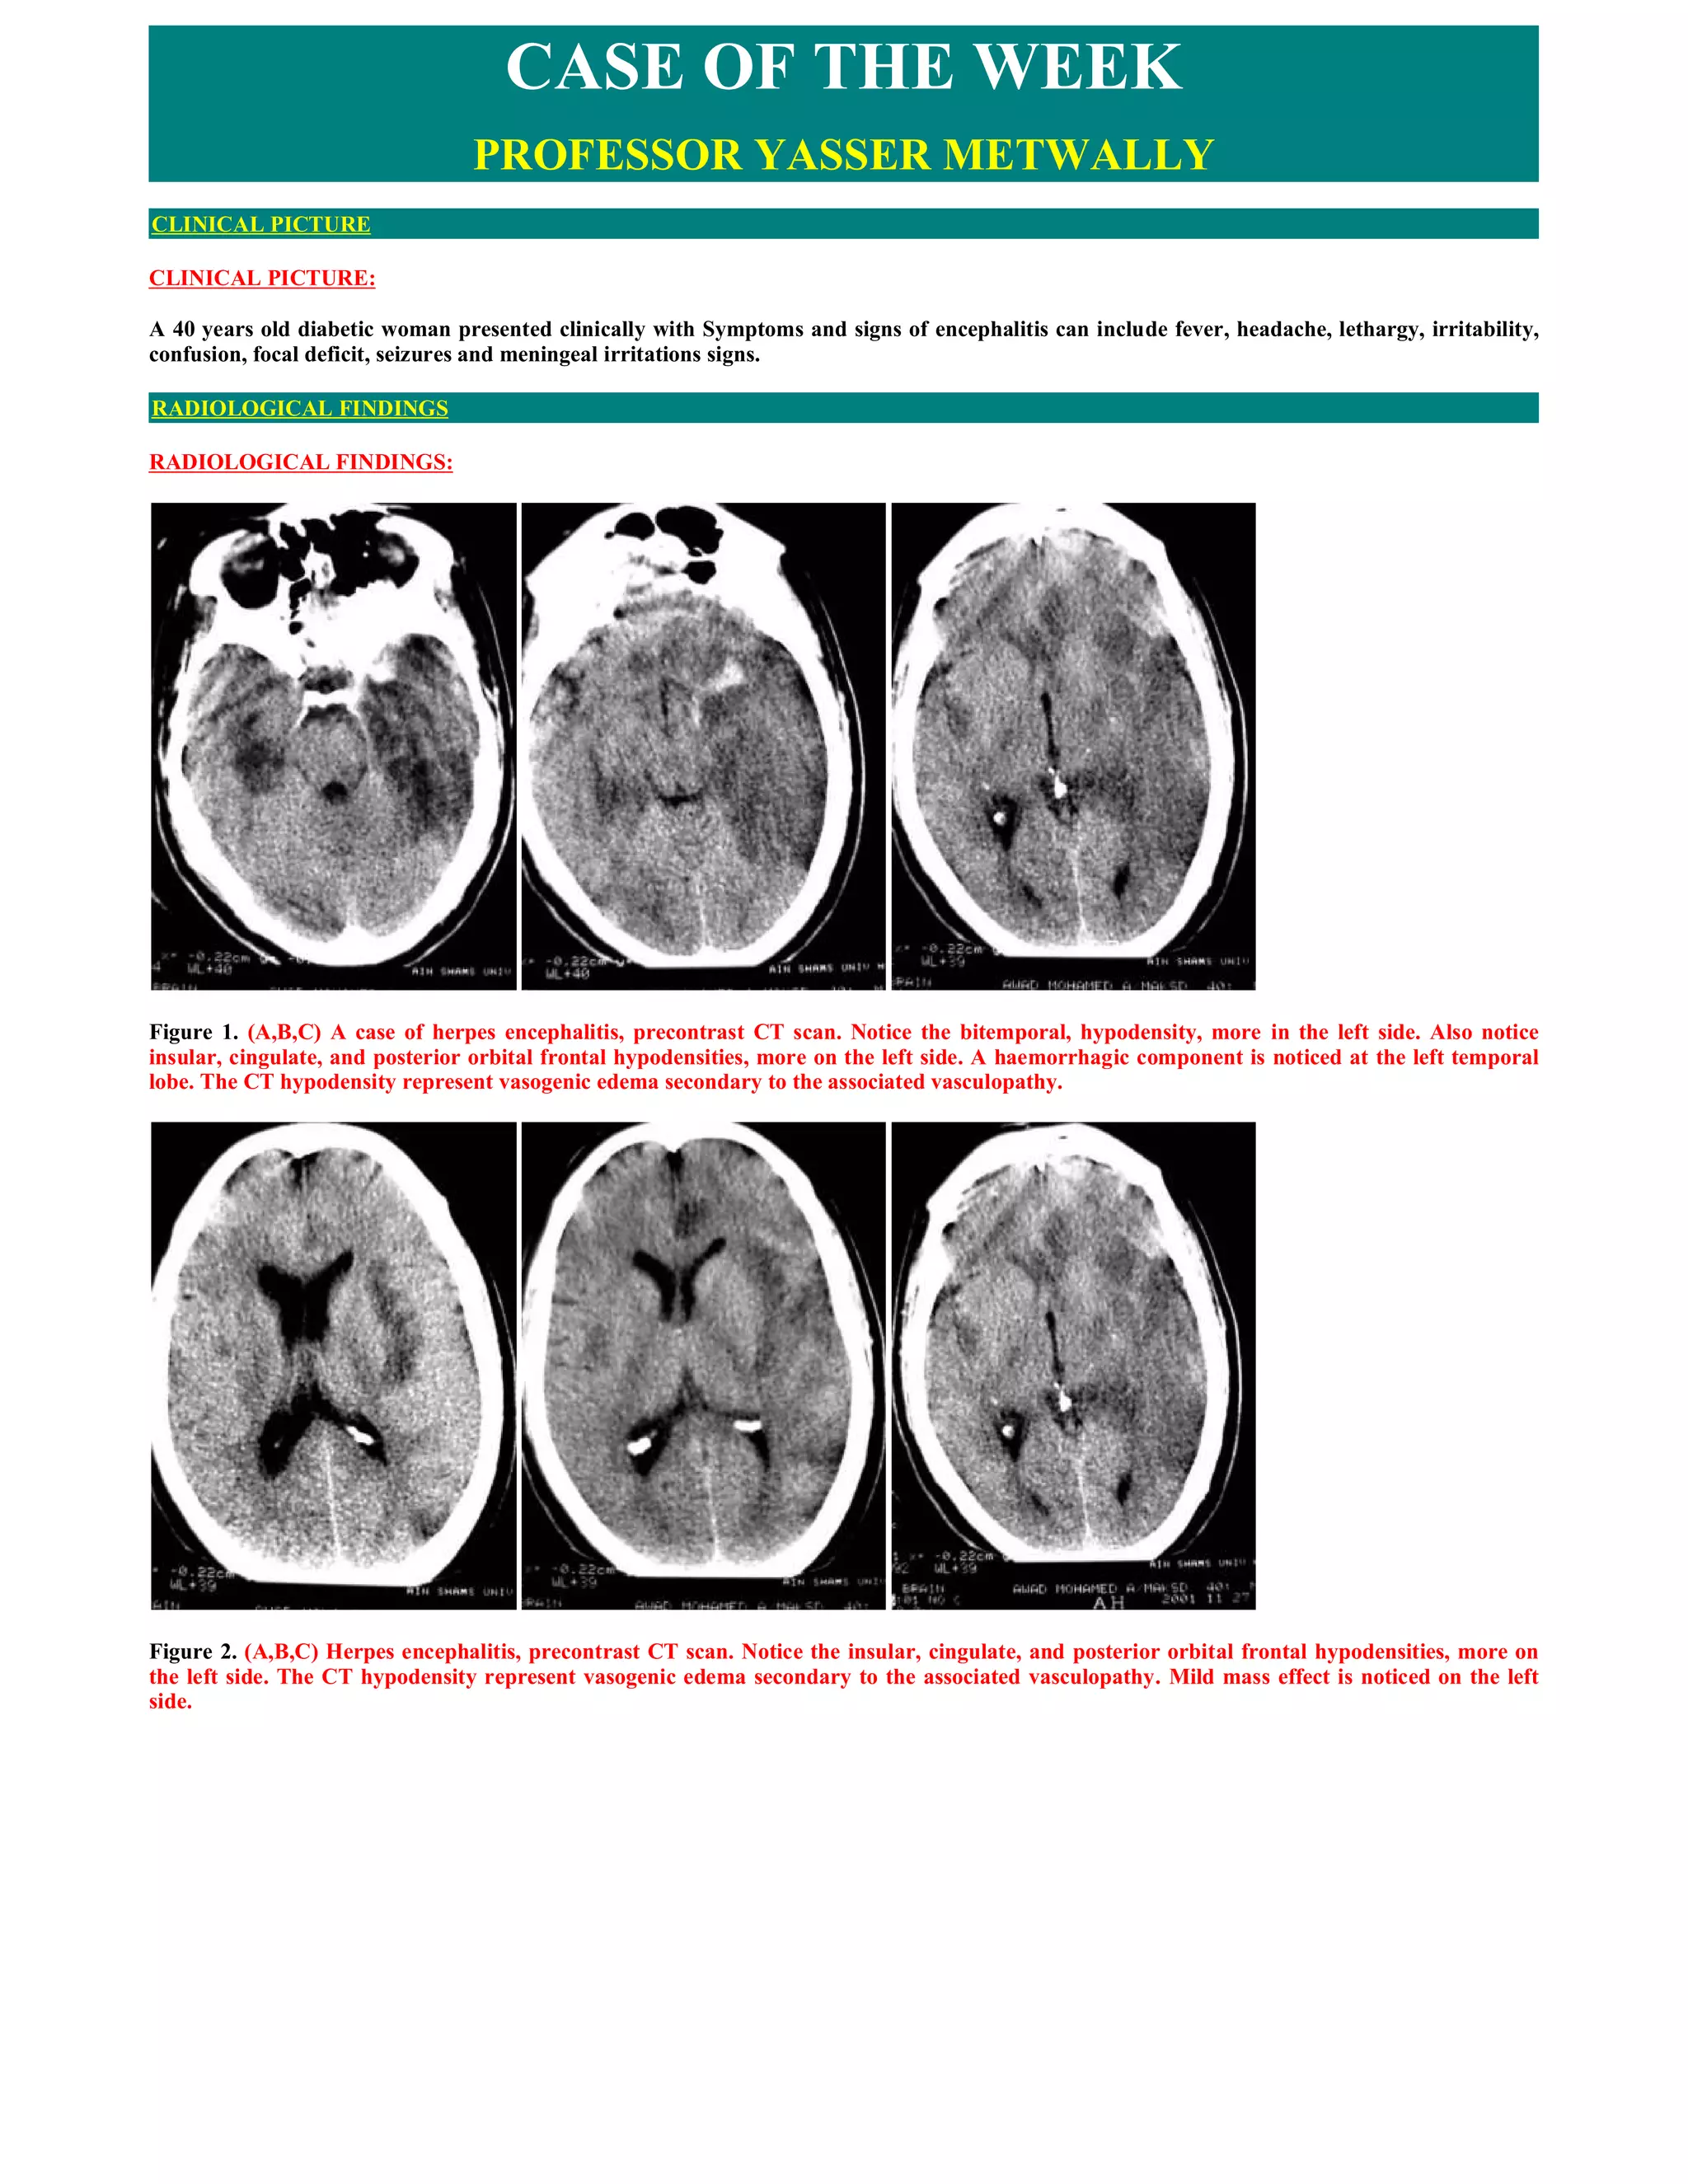

   Neuroimaging

CT scanning reveals hypodense lesions involving the medial temporal regions, with a sharp transition from the hypodense temporal lesion to

normal basal ganglia.[5] Edema and mass effect occur in 80% of cases, and lesions enhance with contrast. MRI reveals a decrease in T1 signal

and an increase in T2 signal in the orbitofrontal and medial temporal lobes and insulae, with abnormalities appearing earlier and more

frequently than with CT.[6] With modern neuroimaging techniques, HSV-1 encephalitis is only rarely confused with cerebritis, abscess, tumor

or infarction. Figure 1 shows typical CT and MRI changes in patients with HSV-1 encephalitis compared with imaging abnormalities in VZV

vasculopathy (see below) and other viral encephalitides.

Figure 1. Typical changes seen on CT and MRI in patients with herpesvirus infections. (A,B,C) Herpes simplex virus 1 (HSV-1) encephalitis: T2-

weighted MRI brain scan demonstrates bilateral involvement of temporal lobes. The exaggerated signal does not extend beyond the insular

cortex (thin arrow), but does involve the cingulate gyrus (thick arrow).

Figure 2. MRI study in a patient suffering from herpes encephalitis, A,B,C MRI T1 precontrast, D,E MRI T2, F,G,H,I are FLAIR MRI images.

Notice the T1 hypointensity predominantly involving the bitemporal cortex more on the right side, the insular, the occipital orbital frontal (F)

and the cingulate cortex, again more on the right side. The T1 involved zones are hyperintense on the T2 and FLAIR studies. Notice that the

encephalitic process is predominately cortical (A,B,C). Temporal lobes involvement is more medially than laterally. The MRI signal changes are

predominantly due to vasogenic edema, the signal intensity of edema is different from the CSF in flair studies.